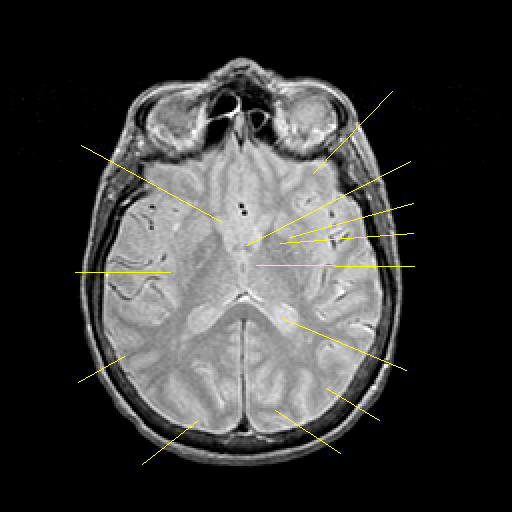

Proton density-weighted structural MR: Slice 28

Pointers

Labeled